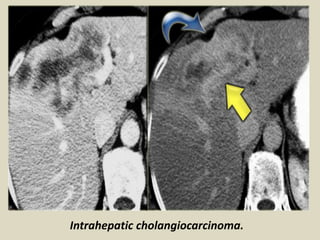

Intrahepatic cholangiocarcinoma About 20% to 30% of

cholangiocarcinomas are peripheral intrahepatic masses.

These masses often appear similar to metastases, and can

easily be misdiagnosed as adenocarcinoma metastases of

unknown primary. Sonographically these masses may have

mixed echogenicity, or predominantly hypoechogenicity or

hyperechogenicity, depending on the predominant underlying

stroma, fibrous tissues versus mucin producing glandular

material. CT and MR appearances are often nonspecific. The

tumors are of lesser attenuation than liver on unenhanced CT

and have a variable enhancement pattern: usually not strongly

enhancing during arterial phases of enhancement, but

showing patchy and usually peripheral enhancement that may

start mildly during the arterial contrast phase and become

more prominent during the portal venous phase.

Intra-hepatic cholangiocarcinoma; A, computed tomography (CT)

image; B, cholangiogram (ERCP) image. Arrows designate the tumor.

Intrahepatic cholangiocarcinoma.